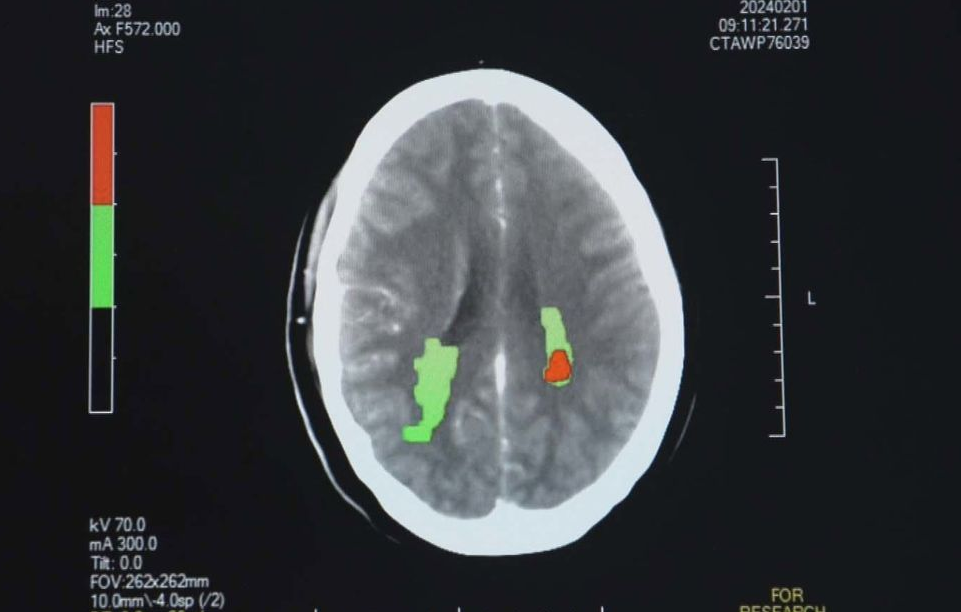

送医就诊后,医院的脑CT结果显示,血栓导致其大脑后部严重缺氧。

“他说话很吃力,而且两眼视力均不佳。第二天我们做的CT显示,他已经没有血块了。”